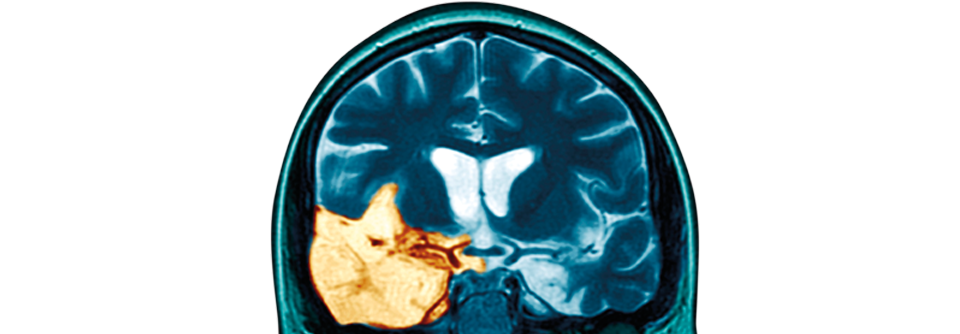

Die psychotischen Symptome der Autoimmunenzephalitis erschweren eine eindeutige Diagnose. Die psychotischen Symptome der Autoimmunenzephalitis erschweren eine eindeutige Diagnose. © iStock/vchal

Die häufigste Form der Autoimmunenzephalitis wird durch Antikörper gegen NMDA-Rezeptoren hervorgerufen. Die meisten Betroffenen (90 %) weisen im Liquor eine Pleozytose auf. Das EEG ist in 90 % der Fälle auffällig. Signalveränderungen im MRT finden sich jedoch nur bei 50 % der Patienten. Deshalb schließen normale MRT-Befunde eine Autoimmunenzephalitis keineswegs aus, sagte Professor Dr. Johann Steiner von der Magdeburger Universitätsklinik für Psychiatrie und Psychotherapie.